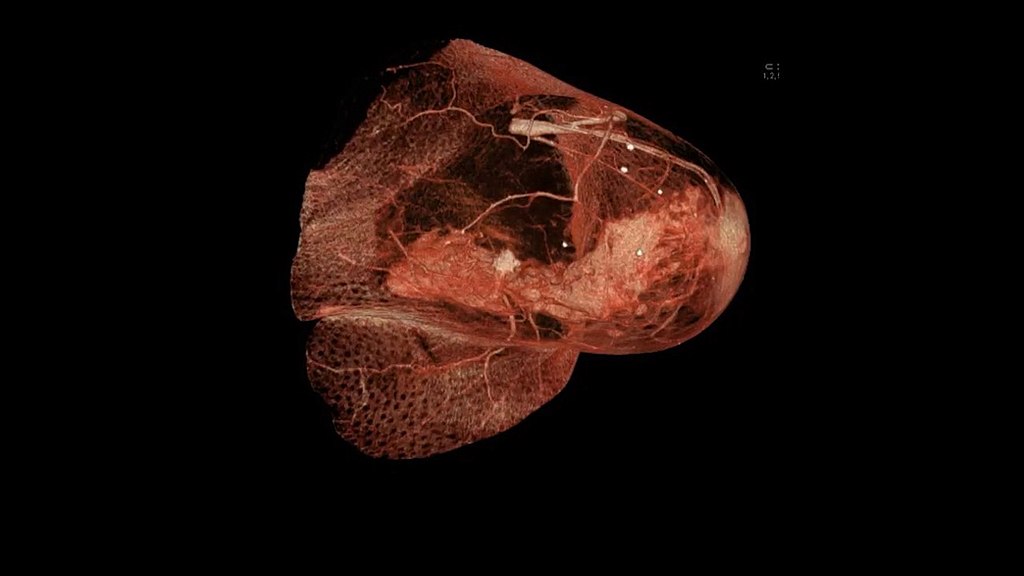

Breast cancer is the most common variety of carcinoma in women, excluding skin cancer.

Invasive ductal carcinoma (IDC) develops when duct lining cells transform and spread into surrounding breast tissue.

Invasive ductal carcinoma (IDC) is the most common type of breast cancer.

The TNM staging system, which stands for tumor (T), nodes (N), and metastases (M), determines the prognosis for breast cancer.

Given that metastasis is uncommon at presentation, spread to axillary lymph nodes is the most helpful prognostic marker.

With sentinel lymph node biopsy, axillary lymph nodes can be assessed for malignant cells.